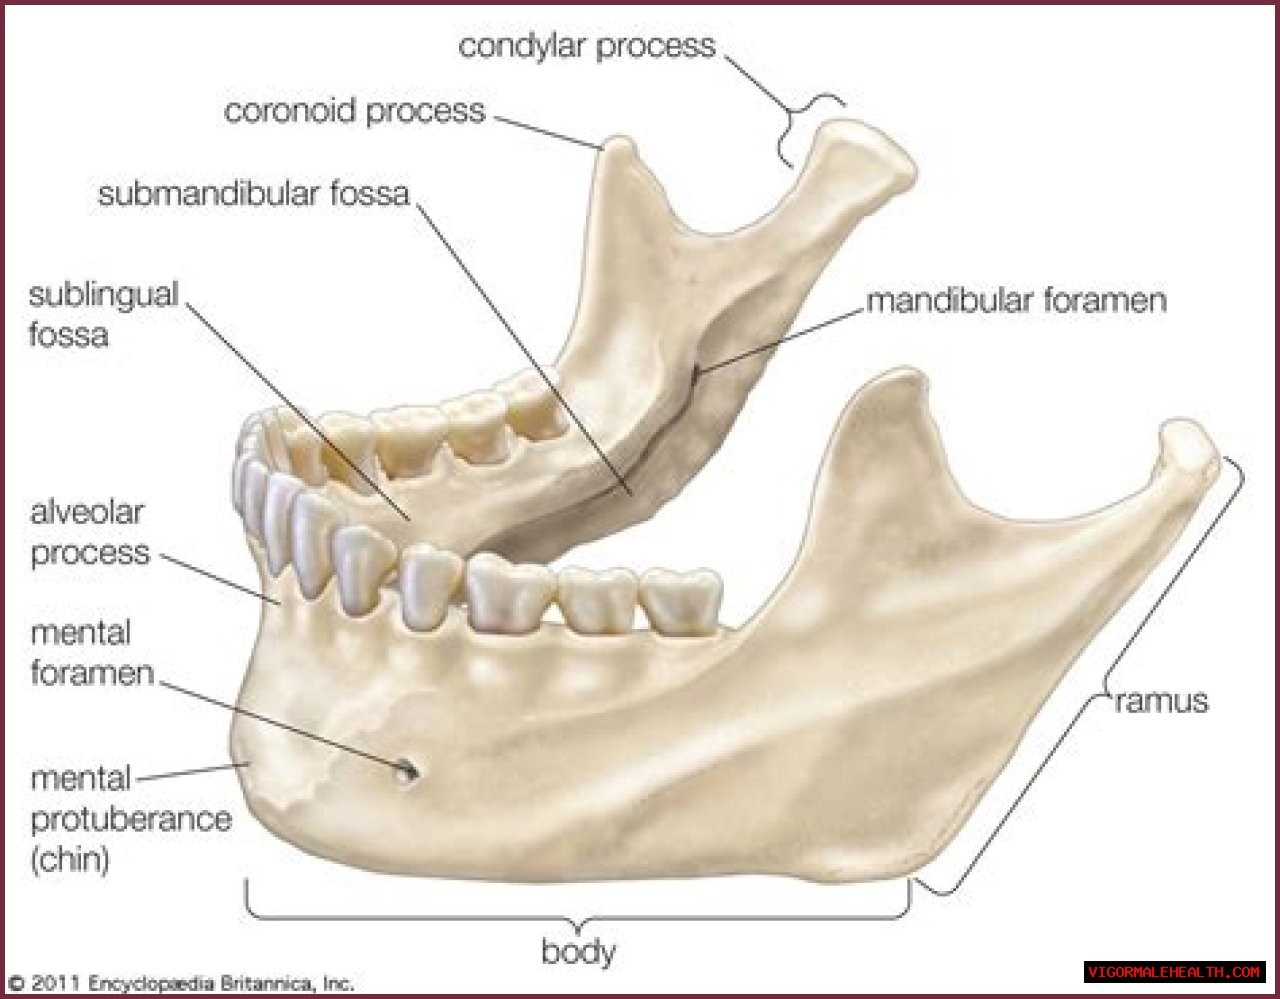

| • | One of the bones, usually bearing teeth, which form the framework of the mouth. |

| • | Hence, also, the bone itself with the teeth and covering. |